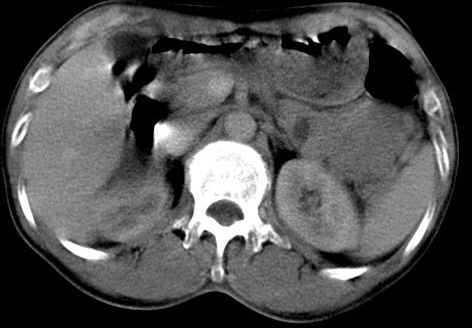

胰尾上有没有占位灶?

肝内占位,考虑肝局灶性结节增生,不除外肝癌.胰尾好象有占位?

以下是引用天山影士在2007-8-28 19:28:00的发言:[br]肝内占位,考虑肝局灶性结节增生,不除外肝癌.胰尾好象有占位?

肝右叶后下内侧段占位:肝癌可能性大。胰腺占位可能,病人没有空腹准备。